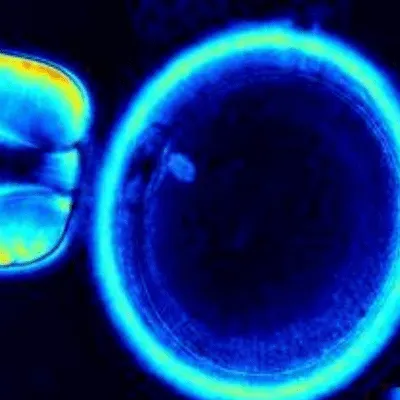

A new method for producing embryos of high quality is ICSI with the help of meiotic spindle imaging. Polarized light microscopy is used to see the spindle. By visualizing the meiotic spindle just before ICSI, it is possible to perform ICSI more safely and at the best possible time during meiosis.

Clinical practitioners and associates employ OSV to check with the oocyte quality before fertilization. Its conjunction with ICSI maximizes the treatment efficacy.

Preparation: It checks with the spindle within the egg by employing polarized light microscopy. With the same, it enables a flawless chromosome division during fertilization.

Imaging: It evaluates the different phases of spindle development.